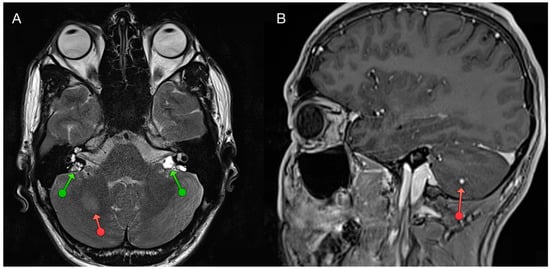

- Halefoglu, A.M. Von Hippel-Lindau Disease Presenting with Cranial and Spinal Hemangioblastomas: MRI Findings. Acta Med. Iran 2023, 61, 115–117. [Google Scholar] [CrossRef]